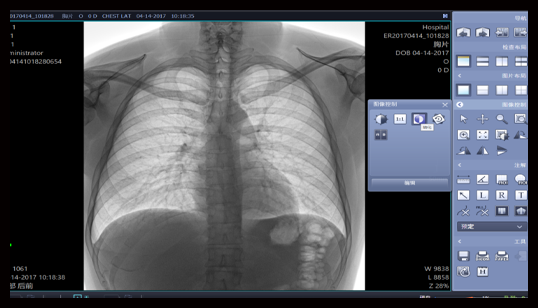

胸片不同尺寸对比

影像清晰,细节突出,无伪影